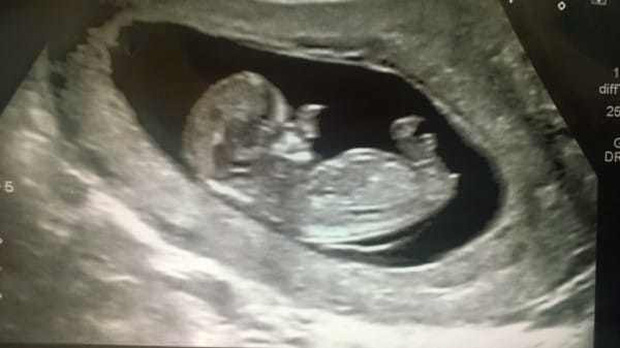

Năm đó, mẹ bé là Amy Poole nhận tin sốc khi mang thai lần hai. Ngay khi siêu âm, bác sĩ đã nhìn thấy điều gì đó bất thường trên khuôn mặt của cậu bé. Trong quá trình chụp cắt lớp xuyên suốt 20 tuần, bác sĩ thấy rằng con trai của Amy có mô mềm phát triển khó kiểm soát xung quanh vùng mũi. Amy biết rằng con trai mình sinh ra sẽ không giống những đứa trẻ bình thường khác, nhưng thực tế tàn khốc hơn rất nhiều so với những gì cô tưởng tượng.